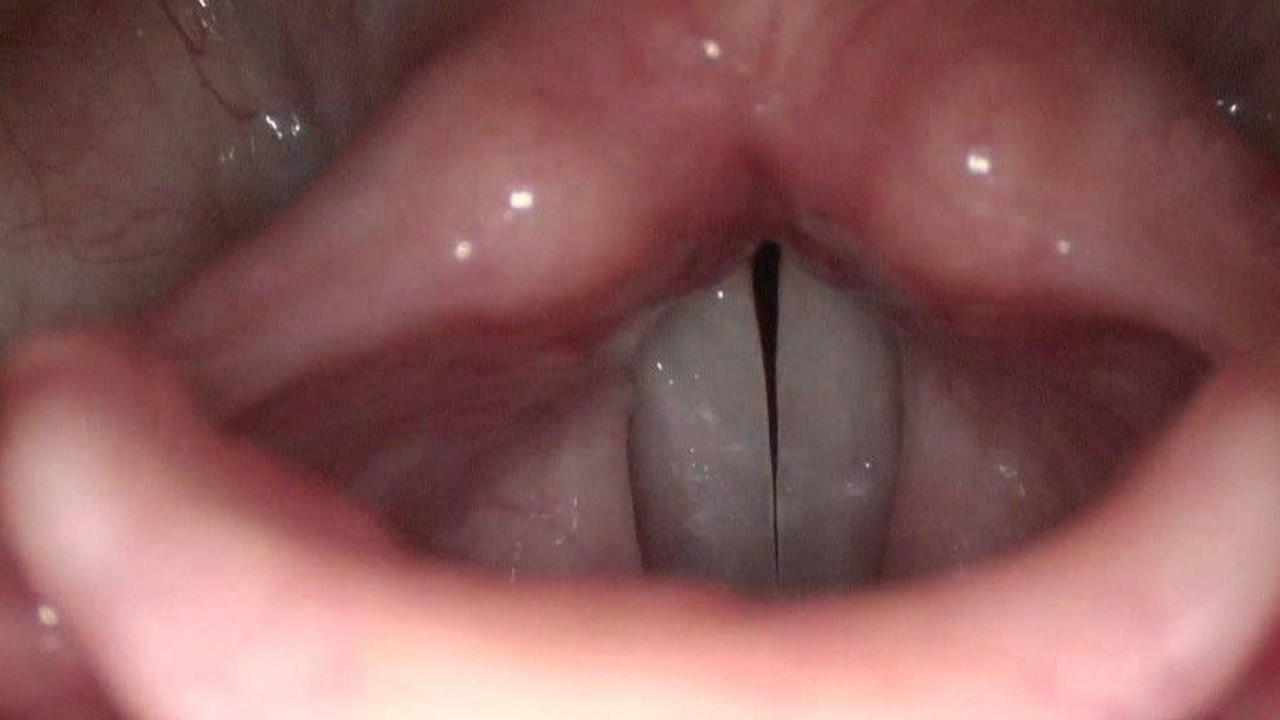

Doç. Dr. Enver, “Sigaranın ses tellerine olumsuz etkileri saymakla bitmez. Bunlar arasında gırtlak kanseri ve nefes darlığı gibi pek çok şey var. Ama bunların yanı sıra kansere neden olmadan da sigara ses telinde yaptığı hasarlara bağlı olarak ses kısıklığı yapabilir. Ses kısıklığı özellikle kadınlarda ses telindeki sigara poliplerine, sigara ödemlerine bağlı olur. Bu erken dönemde ses kısıklığı gibi problemlere neden olurken, zamanın geçmesiyle bu poliplerin büyümesiyle, sigaranın etkisiyle nefes darlığı ve konuşmakta ciddi güçlüklere neden olabilir. Bu hastalar genelde seslerinin kalın olmasından ve telefonda kendilerine beyefendi diye hitap edilmesinden dolayı bize başvururlar. Yaptığımız muayenede ses telindeki sigara polibini gördüğümüz zaman genelde ameliyat kararını alırız. Ameliyat ağız içerisinden ses telindeki polibin çıkartılması işlemine dayanıyor ve boğazda, boyunda herhangi bir kesiğe gerek kalmıyor. İşlem sırasında sesi kaybetmek gibi bir risk yok. Hastalarımız sıklıkla bize bunu sorarlar. Ses ameliyattan hemen sonra iyileşmeye başlıyor. Genelde hastalarımızın beş ile yedi gün kadar hiç konuşmamalarını isteriz. Sonrasında hastalarımız seslerini yeniden kullanmaya başlarlar. Sesin gerçek haline, en güçlü haline ulaşmasıysa birkaç ay sürer. Çünkü ses telinin iyileşmesi zaman alır” dedi.

Doç. Dr. Necati Enver, “Bu duruma sebep olan en temel şey sigara. Sigara aynı zamanda bu problemlere de neden oluyor. Sigaranın dışında boğaz reflüsü, diğer ismiyle gırtlak reflüsü de ses tellerinde bu gibi değişikliklere neden olabilir. Ameliyattan sonra eğer hasta sigara içmeye devam ederse bu durum tekrarlayabilir ve tekrarlayan ameliyatları yapmak hem bizim için hem de hastamız için daha zorlu olacaktır. Hastalarımızın ameliyattan önce sigarayı bırakmasını istiyoruz. Bu sayede ses tellerinin daha iyi iyileşmesi sağlanabilir. Standart ses teli polibi ameliyatlarına göre daha detaylı ve hassas çalışmayı gerektiren bir ameliyat olması nedeniyle iyileşme biraz zaman alabiliyor. Ameliyattan bir hafta sonra hasta sesini kullanmaya başlasa da ameliyattan sonraki iyileşme süreci iki ila dört ay sürmekte. Ve bu sürenin sonunda ses tamamen normale dönebilmektedir. Hastalar ameliyat oldukları günün akşamında sıklıkla evlerine gidebiliyorlar. Ameliyattan sonra herhangi bir ağrı kesici kullanmalarına hemen hemen hiçbir zaman gerek kalmıyor. Ameliyat hasta açısından aslında çok kolay bir işlem. Ama bizim açımızdan mikroskop altında çalışılan çok ince bir iş. Çünkü ses telleri bir parmak boğumu büyüklüğünde çok küçük bir doku. O gördüğümüz polipler de bir veya iki mercimek tanesi büyüklüğünde. Aslında çok küçük bir hastalıktan bahsediyoruz. Ama çok kritik bir yerde olduğu için mikroskop altında çok ince çalışmamız gerekiyor” dedi.